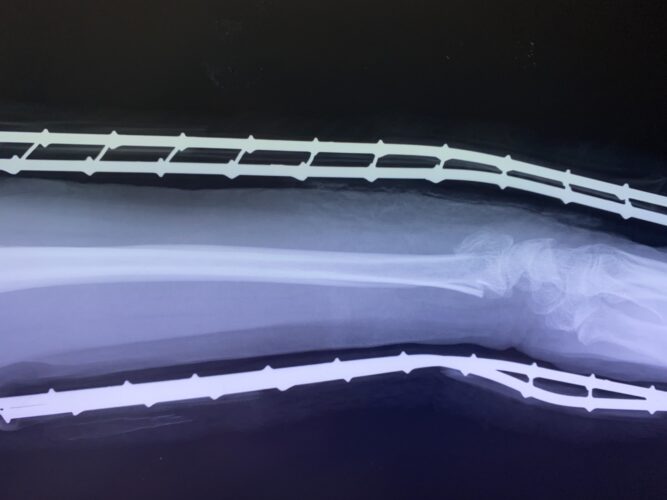

さわやか千葉県民プラザ(前腕骨下端部骨折)

春日部市市民活動センター(前腕骨骨幹部骨折)

第26回整骨研究会「賜恩」研修会開催